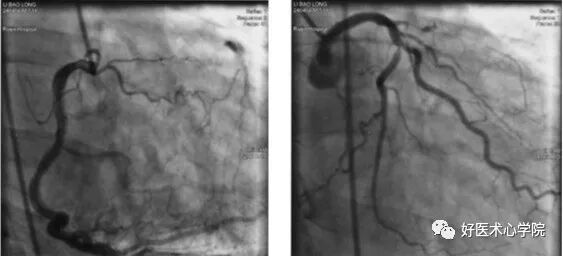

左冠:进入,测压!踩线---出图像,缓慢注入---迅速注入---停止---排空—停止踩线。六个标准体位。

观察压力:压力是否下降,当有左主干病变时会有压力嵌顿,此时不能贸贸然注入造影剂,会出现风险。

右冠:左前斜45°及正头位造影。造影完成,透视下轻提导管,使之脱离右冠口,轻柔抽出导管至体外。结束。